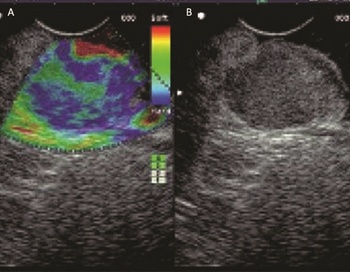

Az elasztográfia az elváltozások további karakterizálását segítő technika. A vizsgálat alapja az, hogy az ultrahangos fejjel a célszerv kompressziója kemény (általában malignus) szövet esetén kisebb feszültséget eredményez, mint puha (általában benignus) szövetek esetén (9. ábra). Így az elasztográfia megmutatja, hogy mely területek a valószínűleg malignusak, és ezáltal irányítja a vékonytű aspirációs mintavételt (Friedberg–Lachter, 2017).

Jegyzet elhelyezéséhez, kérjük, lépj be.!

9. ábra. Pankreász EUH során végzett elasztográfia. A vizsgálat során az elváltozáson (B) belül a kemény, malignus és a puha, benignus területek eltérő színben ábrázolódnak (A), ami segíti az elkülönítésüket és a célzott mintavételt